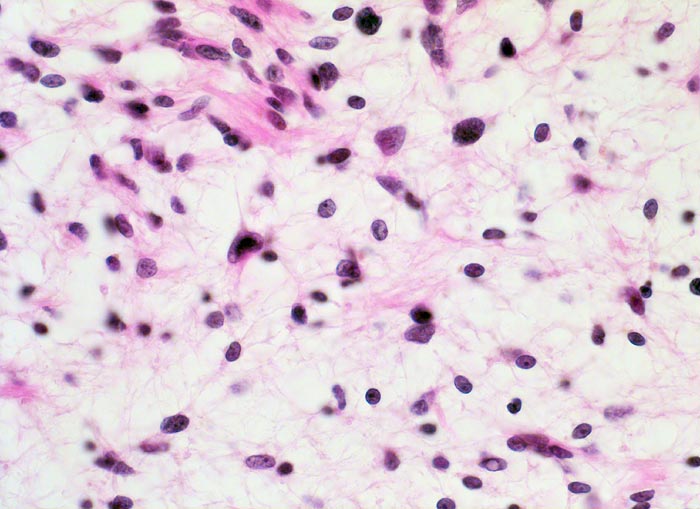

Schwannom: Antoni B Muster

Lockerer Tumorzellverband mit runden Kernen und spinnwebenartigen Zellfortsätzen. Ein Teil der Zellkerne ist hyperchromatisch (Zeichen der Degeneration). Einige weisen intranukleäre Zytoplasmaeinschlüsse auf.

Tumor im Musculus soleus, 2cm Durchmesser

400